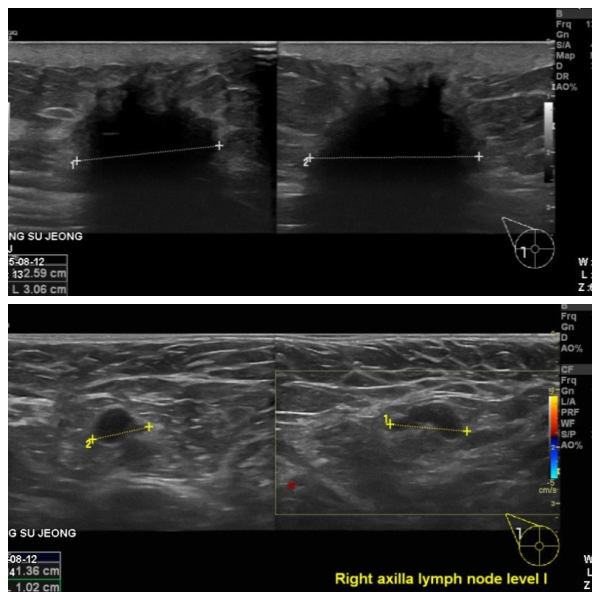

건강검진상 이상 소견을 정밀 검사 의뢰 받아 내원하산 60대 여성분으로 본원에서

우측 9시 방향에 의심스러운 혹 조직검사와 우측 겨드랑이 림프절 비대 세포검사 시행하여 우측 침윤성 유관암과, 겨드랑이 전이로 진단 되었습니다.